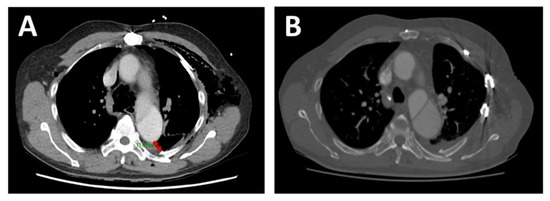

A 66-year-old man presented to the emergency department after being struck by a cyclist. He complained of left-sided chest, shoulder/hip pain, and post-traumatic amnesia. He had a past medical history of hypertension, hypercholesterolaemia, and chronic, residual, Stanford Type A AD, which was repaired in 2014. On examination, he was haemodynamically stable with a brachial blood pressure of 115/71 mmHg, no significant blood pressure differences between arms, a respiratory rate of 22 breaths per minute, and a pulse oximeter saturation of 95% on 2 litres nasal prong oxygen. He had a tender left chest wall posteriorly and laterally, with extensive subcutaneous emphysema over his chest wall and neck bilaterally. He had reduced air entry in his left chest. His had dual heart sounds without murmurs. A computed tomography (CT) scan of his chest showed a comminuted left clavicle fracture, left rib fractures from the second to the ninth, with flail segments from the third to the ninth, and a moderate left pneumothorax (Figure 1 and Figure 2). The sixth posterior rib fracture was only 13 mm away from the aorta (Figure 1 and Figure 3A). The CT also demonstrated that the residual AD had increased in size since the original diagnosis in 2014. A CT of his brain and facial bones showed no new intracranial pathologies or fractures.

Figure 1. Preoperative chest CT. (A). Axial view—preoperative chest CT demonstrating the proximity of the fracture site to the aorta. Subcutaneous emphysema is also seen. (B). Section of longitudinal view—preoperative chest CT demonstrating the proximity of the fracture site to the false lumen of the aorta (~13 mm as indicated by the double-tipped red arrow). Arrow—fracture site; A—true lumen of aorta; F—false lumen of aorta; 6—sixth rib.

Figure 3. Chest CT (axial view)—preoperative and 6-week postoperative images. (A). Preoperative chest CT demonstrating the proximity of the sixth rib fracture site to the false lumen of the aorta (~13 mm as marked by the double-tipped red arrow). (B). 6-week postoperative chest CT showing in situ RibFixTM plates.